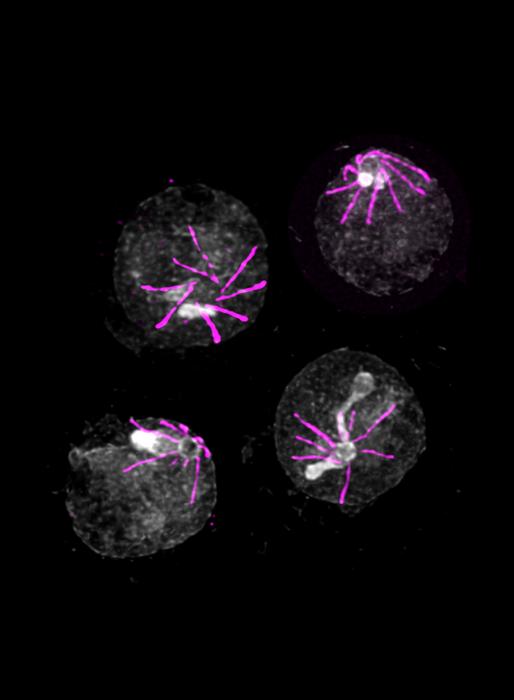

There are small molecules absent in the blood but present in the mosquito that the parasite is able to detect. "Starting from this single known element, we have identified a sensor that enables the parasite to detect the presence of these molecules when it is ingested by a mosquito", explain Ronja Kühnel and Emma Ganga, PhD students in Mathieu Brochet’s laboratory and first authors of this study. "This sensor is made up of five proteins. In its absence, the parasite does not realize that it has left the bloodstream for the mosquito, and is therefore unable to continue its development".

Surprisingly, this sensor is also present at other stages of the parasite lifecycle, notably when the parasite has to leave the red blood cell. "We then observe exactly the same mechanism: without this sensor, Plasmodium is trapped in the red blood cells, unable to continue its infection cycle." However, scientists have not identified the human molecules detected by the parasite; identifying them could provide a better understanding of how waves of fever are caused by Plasmodium.